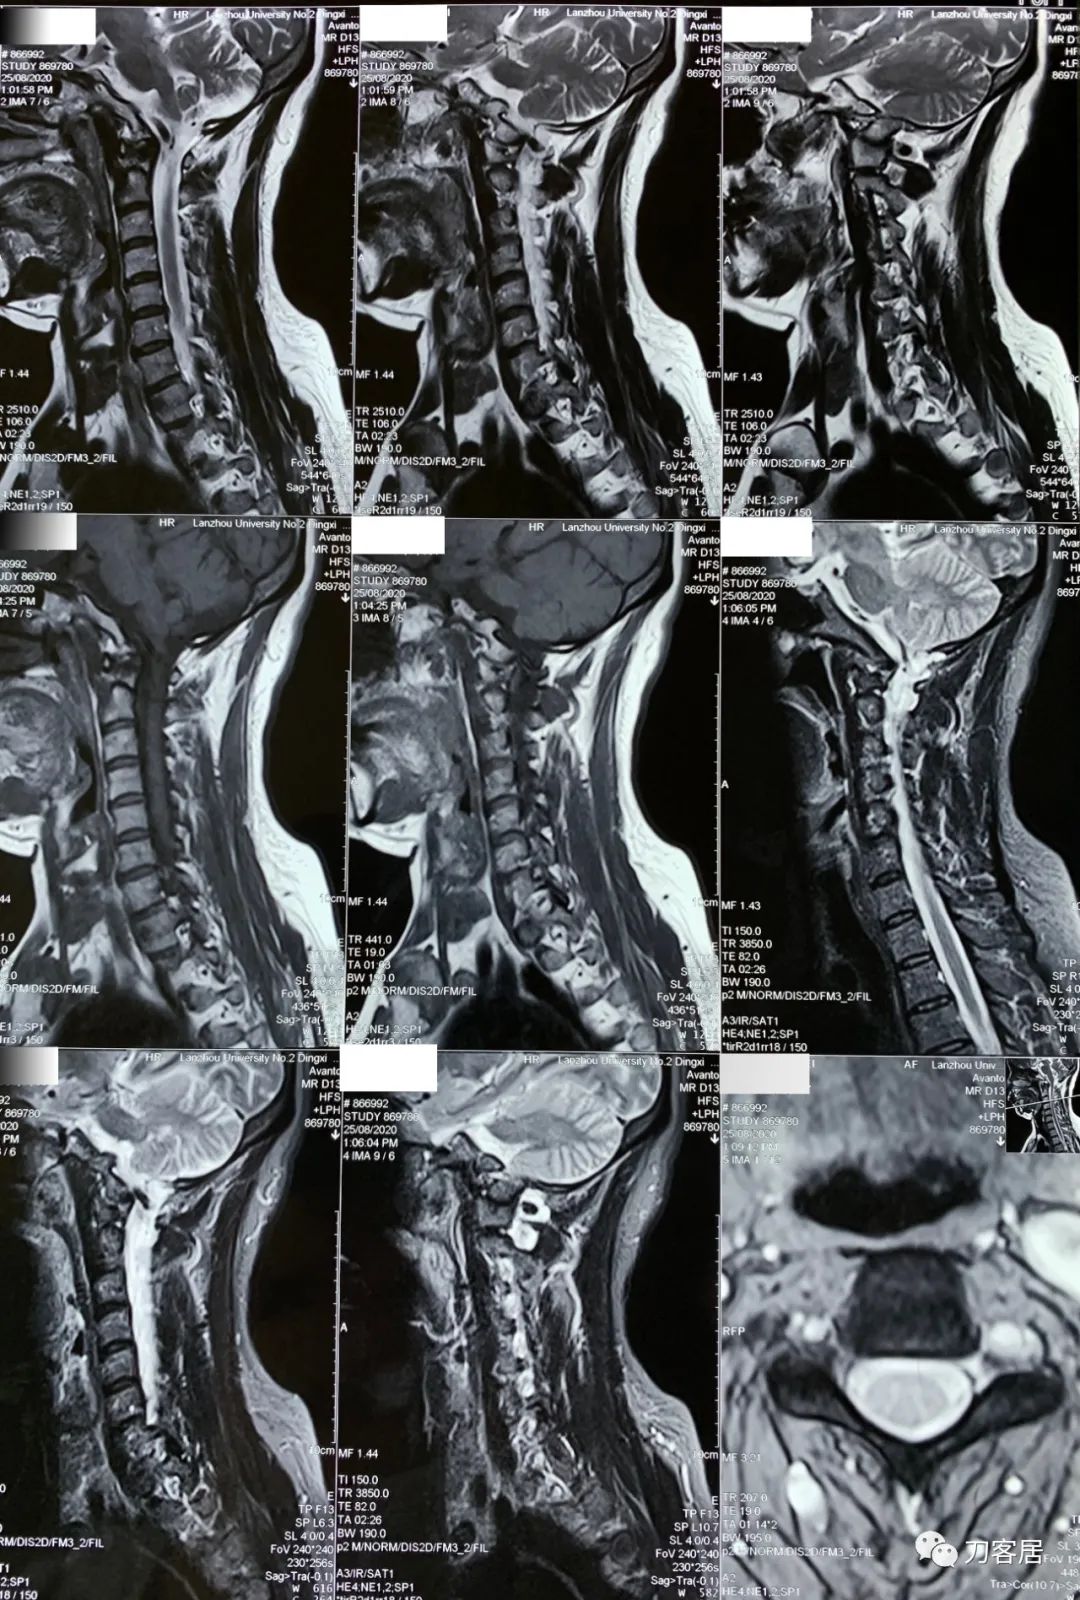

2021年12月12日去渭源县医院做颈椎腰椎MRI,提示1.腰椎侧弯畸形并骨质增生,2. L5S1椎体终板炎(I型), 3. L1-S1椎间盘变性并腰2-4,腰5骶1椎间盘膨出,腰4-5椎间盘突出并相应平面继发性椎管狭窄。2020年12月中旬于渭源县医院行骶管注射2次6针后睡眠改善,

2021年5月17日,西京医院骨科门诊找我就诊,自带影像学检查资料提示腰椎侧弯,腰3-4,腰4-5椎间盘突出,黄韧带肥厚,椎管狭窄。

从这个患者的影像资料分析,颈椎间盘突出问题不大,没有明确的上位神经元损伤表现,所以,不考虑颈椎和胸椎问题。腰椎侧弯畸形,但不严重。因为存在腰椎侧弯,使得腰椎MRI在扫描切面的时候,显示的椎间盘突出或椎管狭窄会有一定的误差,所以,又加做了经椎间盘的CT平扫,影像表现并不严重,综上,腰椎间盘突出,腰椎管狭窄,腰椎侧弯,不考虑手术治疗。同时,患者的主要痛苦是心理疾病,而不是器质性疾病,所以,以心身疾病治疗为主。虽然患者骨密度检查结果提示正常,但X线片显示骨质疏松,且其症状也与骨质疏松的症状有符合之处,比如静息痛,不能入睡,动作及姿势变换时痛加重等,所以,给予实验性抗骨质疏松治疗,以观疗效。

3. 2020年12月11日,在甘肃省中医院脊柱骨二科看病,吃中药,治疗半月,中途12月12日去渭源县医院做了核磁检查,提示腰椎侧弯畸形并骨质增生,腰5骶1椎体终板炎(I型), 腰1-骶1椎间盘变性并腰2-3,腰3-4,腰5骶1椎间盘膨出,腰4-5椎间盘突出并相应平面继发性椎管狭窄。